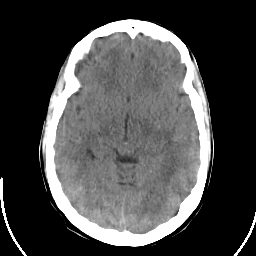

Sarcoma: Roentgen-ray CT -- Slice #10

[Home][Help][Clinical] Slice 10